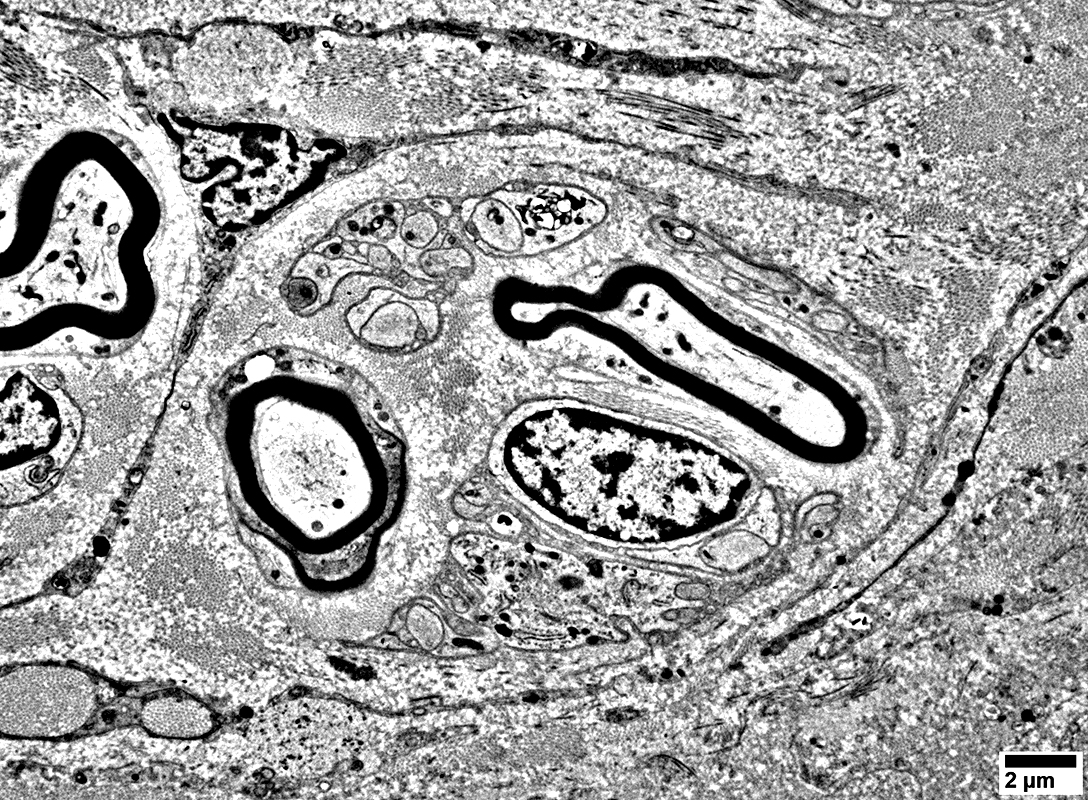

Regenerated Axon Clusters within Neuroma

Axons in fascicles tend to be thinly myelinated for their size

Small minifascicles contain 1 to 30 myelinated axons

Minifascicles

Contents

Thinly myelinated axons

Clusters of Schwann cell processes (Büngner bands)

Collagen

Surrounded by

Perimysial cell/Fibroblast process

From: R Schmidt

Clusters of thinly myelinated axons

Neuroma: Minifascicles

Small minifascicles: Contain 1 or 2 thinly myelinated axons (Top)

Fascicle with normal organization (Bottom left)

Toluidine blue stain

Small minifascicles: Contain thinly myelinated axons